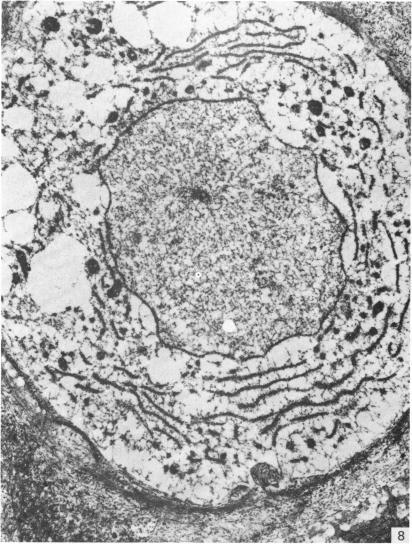

来自矮胖(stm)突变小鼠下颌髁突的异常软骨。

Abnormal cartilage from the mandibular condyle of stumpy (stm) mutant mice.

The mammalian mandibular condyle is composed of secondary cartilage and may thus be susceptible to genes causing achondroplasia and which result in abnormal++ primary cartilage formation. This paper describes the secondary cartilage in the mandible of the stumpy achondroplastic mutation in the mouse: both primary and secondary cartilage are affected by the gene.

哺乳动物的下颌髁由继发性软骨组成,因此可能易受导致软骨发育不全并致使初级软骨形成异常的基因影响。本文描述了小鼠短粗型软骨发育不全突变体下颌骨中的继发性软骨:初级软骨和继发性软骨均受该基因影响。